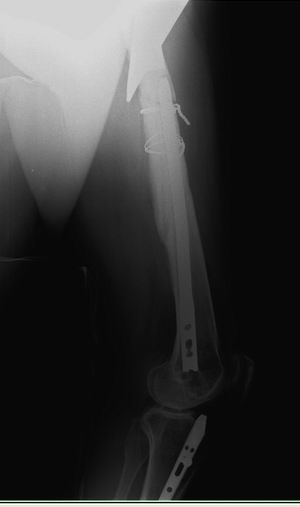

Уважаемые коллеги!Хочется услышать ваше мнение. Пациентка 48 лет, без вредных привычек, получила свежую травму (с\3 диафиза правого бедра) при падении с лестницы. Ранее (8 лет назад) была множественная травма, на бедре – перелом с\3, выполнен остеосинтез DFN Synthes (в др. ЛПУ). Перелом диафиза консолидировался очень медленно, от реостеосинтеза категорически отказывалась, в результате к 2 годам наступило сращение. Беспокоили боли при нагрузке, на рентгенограммах – зона разрежения вокруг кончика (проксимального) стержня и проксимальных винтов, согласилась лишь на удаление дистальных винтов для динамизации стержня. Пациентка пропала из поля зрения. Затем спустя 2 года при падении получает чрезвертельный перелом, выполнен остеосинтез бедренным винтом ( DHS ).Планирую удаление имплантов (кроме проволоки), рассверливание костно-мозгового канала (сейчас стоит гвоздь 10 мм, попытаюсь рассверлить до 14-15 диаметра, чтобы поставить 12 мм или 13 мм гвоздь), внутрикостный остеосинтез блокированным стержнем (динамически).

Теперь вопросы: 1.Так как нет оригинального инструмента Synthes , то интересует резьба на конце стержня какой диаметр и метрическая ли она. 2.Есть ли заглушка на стержне (мне так кажется, что нет). 3.Нужно ли заполнять полость аутокостью от шеечного винта. Извиняюсь за качество снимков. Спасибо! С уважением, А.Минервин.

Уважаемые коллеги! Кратко отчитаюсь по представленному случаю.

Вчера пациентка прооперирована. Как и ожидалось, основные трудности были с удалением металла. Удаление произведено из трех доступов: где пластина 8 см, блокирующие винты- 5 см, сам стержень 3 см.. Дольше всего пришлось извлекать end cap у стержня, далее сломался 1 винт в пластине (долото в помощь, но аккуратно, только наружный кортикал, из внутреннего - выкручен). Рассверлил дистальный отломок до 14 мм, проксимальный до 13 мм. Стержень ChM, диаметр12 мм. Долго существующая деформация бедра предопределила и положение стержня в проксимальном отломке – тесно к наружному кортикалу, надеюсь, до угрожающего конфликта не дойдет.

Спасибо всем участникам! Критика приветствуется J.

P.S. Резьба на стержне действительно М8. Если кому нужно, в сети есть брошюрка Synthes Nail Removal с указанием резьб.

С уважением, А.Минервин.